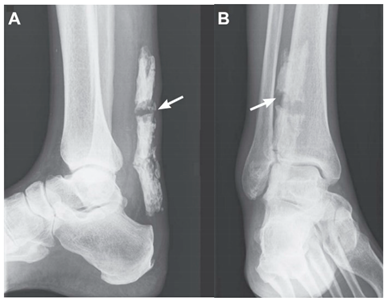

| Wick and Rieger, 2008 a [33] | A 69-year-old man. This image submission includes two x-ray images of a complete rupture of a calcified Achilles’ tendon of a 69-year-old male (Images A and B). Arrows indicate the presence of a complete rupture of the calcified Achilles Tendon. The man reported previous partial cutting of his Achilles’ tendon when he was a teenager. The man felt a sudden pain while standing from a seated position, where he proceeded to the emergency room for imaging. | ![]() |